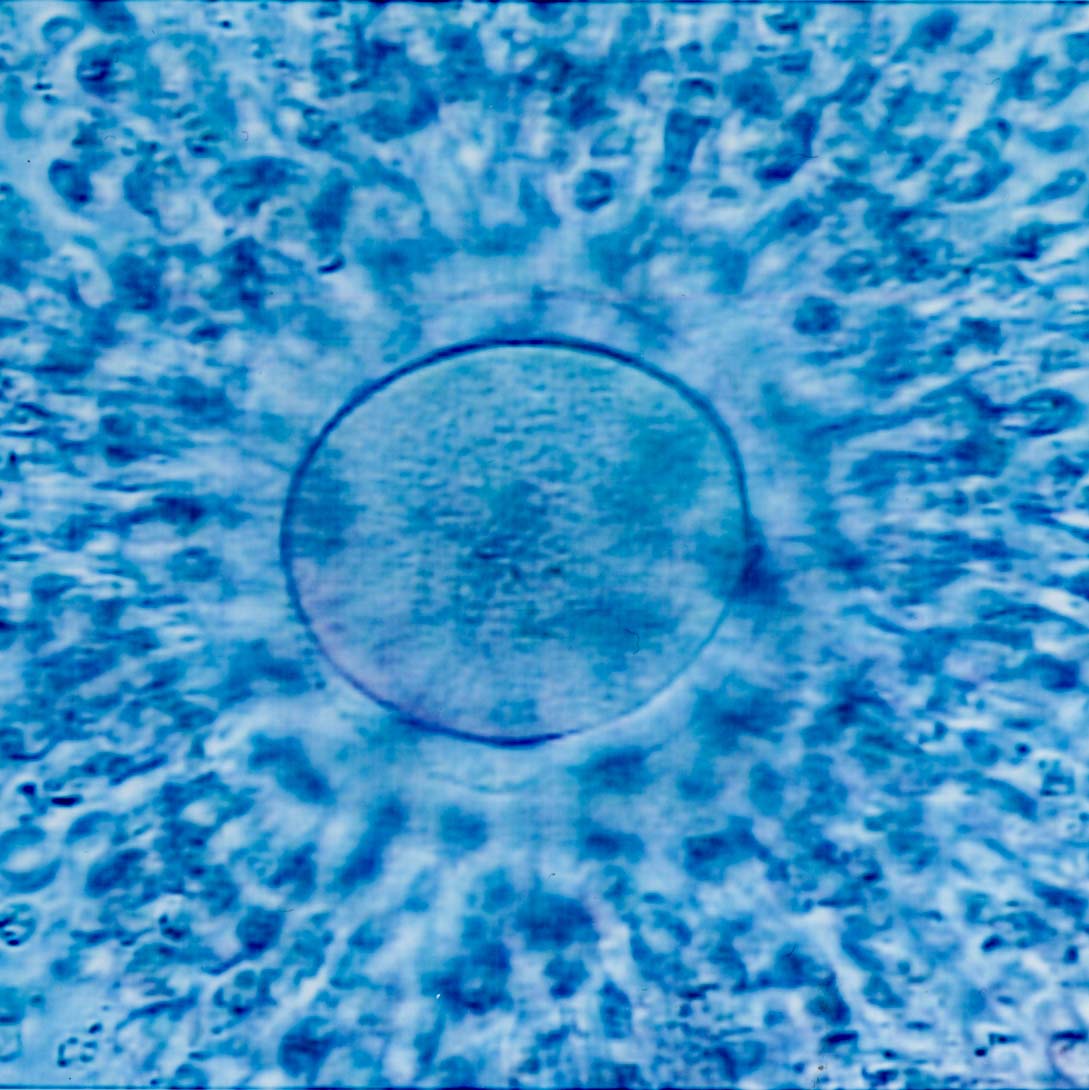

The process of freezing a woman’s eggs necessitates that the eggs are actually removed from her uterus, frozen and stored, so that they can be reinserted years later in their original healthy state. The typical cost of this amounts to approximately $10,000 per procedure, and an additional $500 annually for storage. Apple and Facebook have offered up to $20,000 for female staff who would like to take advantage of this procedure.